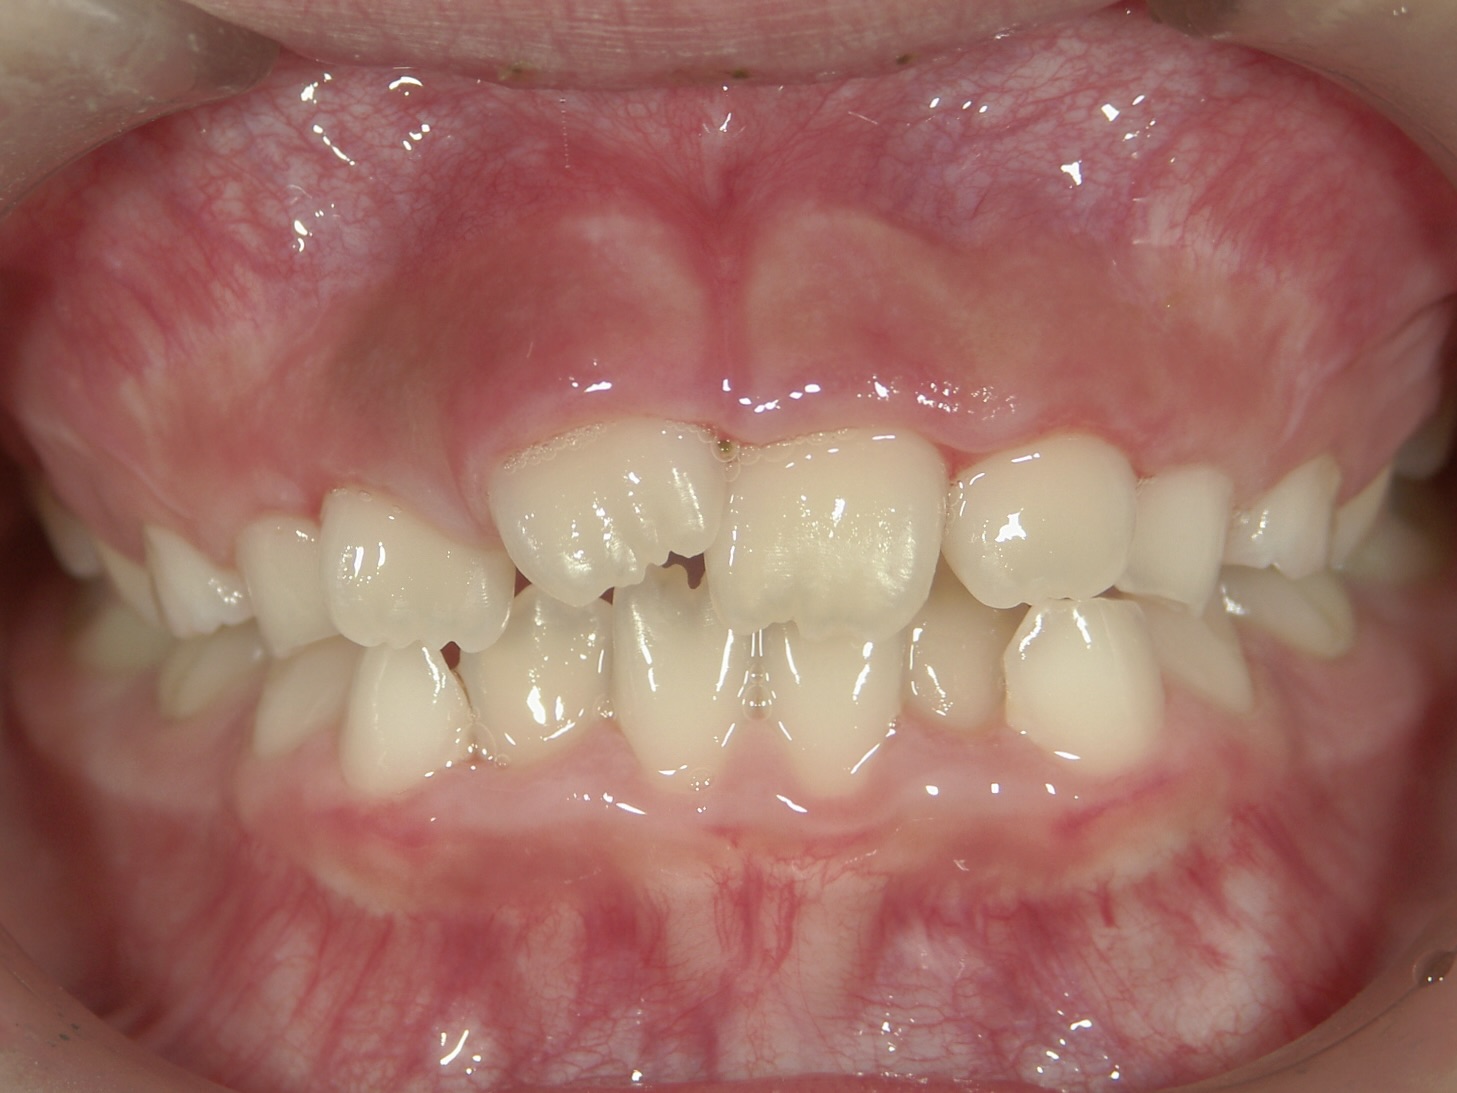

2016年 9歳

前歯が重なって生えてきている。この時点で歯が並ぶスペースが少ないことは十分予想できる。